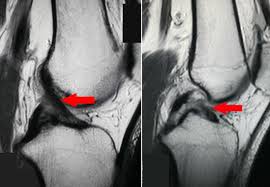

– MRI or CT scan

This is another imaging test which involves assessment of detailed images of soft tissues, discs or nerves. It helps identify the reason behind leg pain, which may be due to conditions such as herniated disc, spinal stenosis, nerve compression and sciatica.